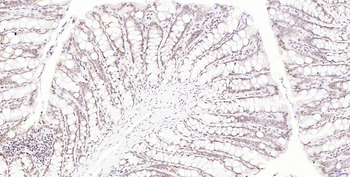

50 μl, 100 μl - KLF4 Recombinant Rabbit Monoclonal Antibody [orb608075]Featured

FC, ICC, IF, IHC-Fr, IHC-P, WB

Human, Mouse, Rat

Rat

Rabbit

Recombinant

Unconjugated

200 μl, 50 μl, 100 μl - Featured